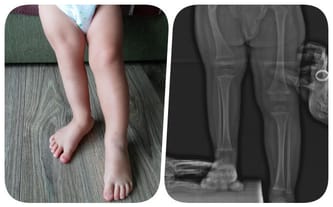

Nie wiedzieliśmy, że informacja, która całkowicie wywróciła nasz świat, dopiero nadejdzie. Kubuś urodził się z niedorozwojem kości udowej. Choroba pociąga za sobą szereg innych nieprawidłowości w budowie stawu biodrowego, a także znaczną różnicę w długości nóżek. Obecnie wynosi ona 8 centymetrów. Co gorsza, ostateczna różnica ma wynieść aż 21 centymetrów! Ratunkiem dla Kubusia są operacje, które mogą sprawić, że będzie sprawnym chłopcem! Doktor Paley daje nam 99% szans na całkowitą sprawnośc - tej szansy nie możemy zmarnować!